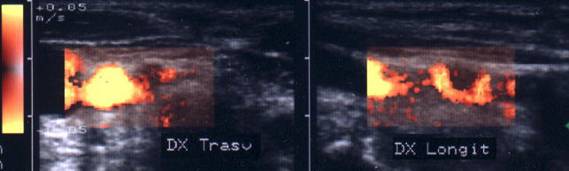

ecocolordoppler si powerdoppler- acelasi nodul

Vascularizatie interna, mai evidenta in powerdoppler.